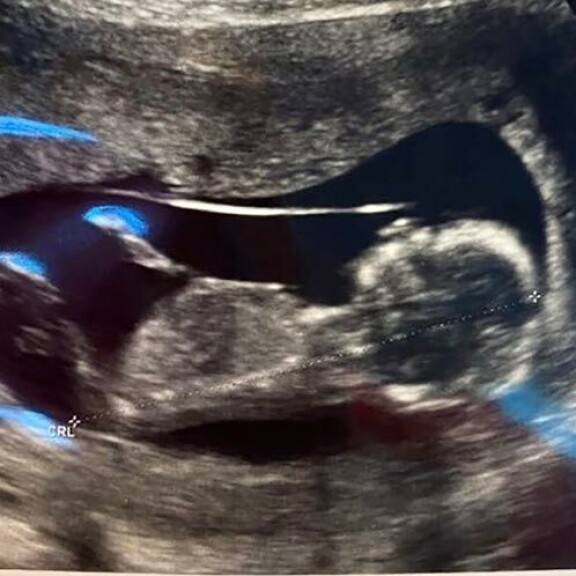

Tosi-tv-tähti Henna Kalinainen, 31, on raskaana rakkaalleen Jarkolle. Raskaus on edennyt jo toiselle kolmannekselle.

Kohukaunottaren jättiyllätys! Henna Kalinainen: Saan jouluvauvan!